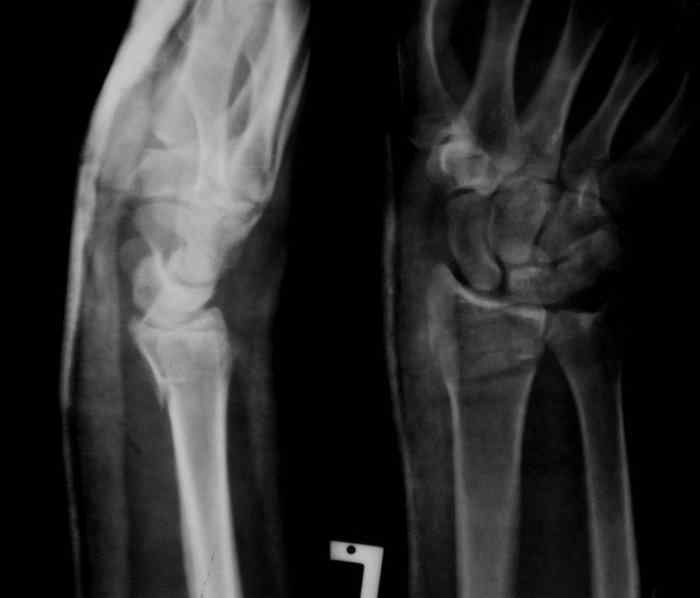

Sergey Melashenko 14 Декабрь 2007, 02:04

Под проводниковой анестезией произвел аккуратную одномоментную репозицию, фиксацию гипсовой повязкой в положении умеренной экстензии. Думаю неплохо получилось. Мягкие ткани не вызывали опасений в плане Зудека.

Спасибо.

13.12.2007.jpg

37KB (38539 bytes)